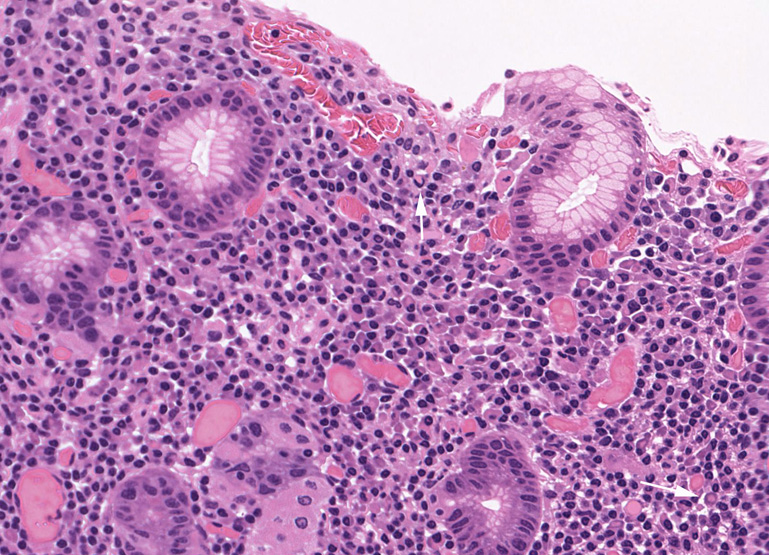

Lymphoepithelial lesion(LEL)

胃MALT lymphomaに認められたlymphoepithelial lesion

腫瘍リンパ球の浸潤で腺窩がボロボロに破壊されている

- LELは胃, 肺, 甲状腺ではほぼ必発で診断的価値が高いが腸管の症例では無いか, あっても顕著ではなく臓器間に差がみられる。唾液腺では非腫瘍性疾患でも認められるので注意が必要である。*6

- 疑い例はcentrocyte-like cellが反応性濾胞を取り囲み粘膜固有層にびまん性に浸潤すると同時に小グループで上皮に浸潤する。